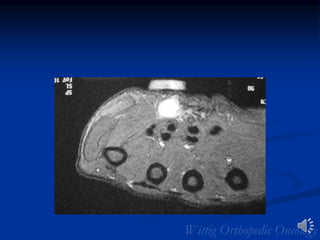

MRI:Leiomyosarcoma of Vastus

Medialis Muscle

MRI with Gadolinium

Leiomyosarcoma of Vastus Medialis

Leiomyosarcoma

• Remainder of lesions in GU and GI tracts

• 5th and 6th decades

• Metastases common

• Imaging similar to MFH/fibrosarcoma

• Extremity lesions usually intramuscular

• Central necrosis/hemorrhage common

• Calcification/osseous invasion rare